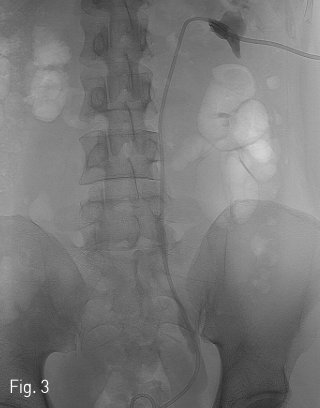

Fig 3

Ureteral stent was inserted left ureter through isolated calyx and neoinfundibulotomy.

환자는 왼쪽 신장의 isolated calyx에는 8.5Fr. drainage catheter가 insertion 되어 있고 left renal pelvis에는 double J stent가 insertion 되어 있는 상태로 prone position을 취하였다. 기존의 drainage catheter에 0.035inch 유도 철사(Terumo, Tokyo, Japan)를 insertion 하고 catheter는 제거한 후 8Fr. Sheath(Boson, Shrewsbury, USA)를 삽입하였다. 조영제(Visipaque, GE healthcare, Chicago, USA)를 주사하여 tubogram을 시행하였고 isolated calyx 와 콩팥깔때기와의 연결성은 없었다. (Fig.1B) 초음파 유도 하에 21G 천자바늘(Cook, Bloomington, USA)로 isolated calyx를 천자하고 X선 투시하에 천자바늘을 콩팥깔때기에 insertion 되어 있는 double J catheter를 향해 진입시켰다. (Fig. 2A, B) 천자바늘의 속심을 제거한 후 X선 투시하에 조영제를 주사하여 isolated calyx를 지나 콩팥깔때기가 천자된 것을 확인하고 0.018inch 유도 철사(A & A, Gyeonggi, Korea)를 넣었다. (Fig. 2C) 이후 천자바늘을 제거하고 단일 막대 접근 장치(yellow sheath; A & A, Gyeonggi, Korea)를 이용하여 접근로를 확보했다. 유도 철사와 metal stiffening inner cannula를 제거하고 0.035inch 유도철사(Terumo, Tokyo, Japan)를 넣고 6mm x 4cm balloon(Boson, Shrewsbury, USA)을 이용하여 isolated calyx와 콩팥깔때기 간 neoinfundibulum 을 재건하였다. (Fig. 2D) 삽입되어 있는 유도 철사를 통해 isolated calyx, neoinfundibulum 그리고 콩팥깔때기를 차례로 통과하도록 10.2Fr. nephrostomy catheter(Cook, Bloomington, USA)를 위치시켰다. (Fig. 2E) 4일 후 기존의 10.2Fr PCN catheter insertion site를 통하여 10Fr sheath(Terumo, Tokyo, Japan)를 insertion 한 뒤 0.035inch 유도철사(Terumo, Tokyo, Japan)를 방광까지 진입시킨 뒤, 26cm 7Fr double J stent(Boson, Shrewsbury, USA)의 원위부는 방광에 위치시키고 근위부는 isolated calyx에 위치시켰다.(Fig. 3) 이후 isolated calyx로의 접근로에는 10.2Fr. nephrostomy catheter(Cook, Bloomington, USA)를 삽입하고 시술을 종료했다.